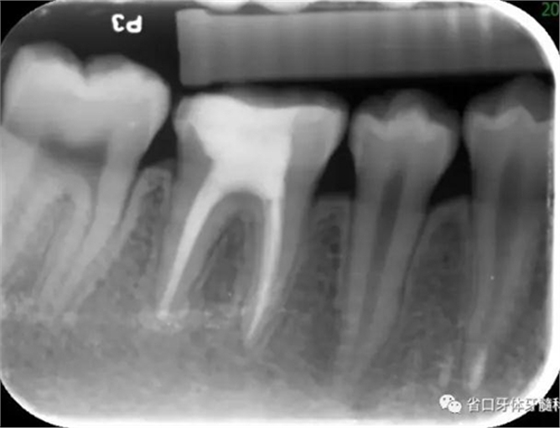

圖4 根管治療術后17個月:根分叉和根尖低密度影基本消失